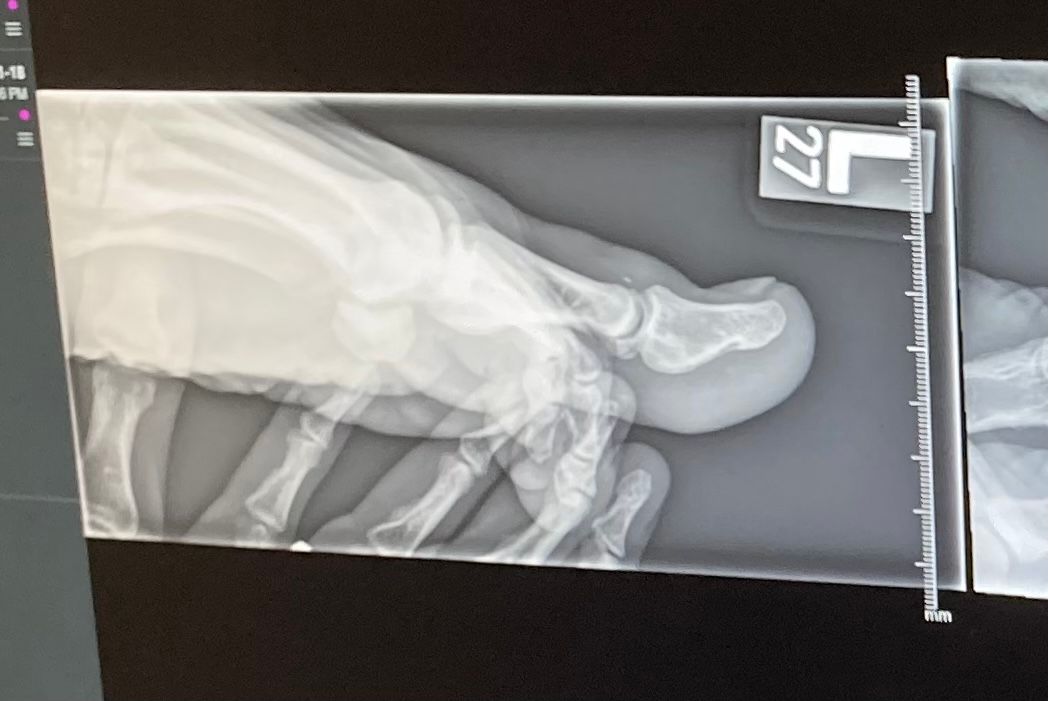

We went to the ER where they did an X-ray and I found out that it’s not broken, just dislocated. The doctor gave me some local anesthetic and pulled the toe until it popped back in. I've had better times, but it's all good now as the toe is in its normal position.